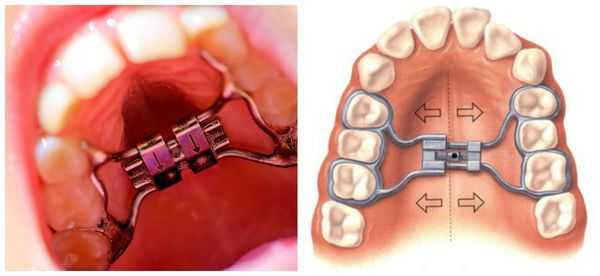

Клиническая картина аномалии зубочелюстной системы значительно осложняется при присоединении деформации зубных рядов, сопровождающей частичную потерю зубов. В настоящее время мезиальный наклон моляров нижней челюсти - часто встречаемая патология зубочелюстной системы, а ее лечение чаще всего осуществляется с помощью брекет-системы и микроимплантатов. До сих пор проблеме оптимальных методик исправления положения зубов уделено недостаточно внимания, отсутствуют данные о пределах ортодонтического лечения данной патологии. Предложенная нами методика, основанная на детальном изучении положения зубов в норме, позволяет обосновать перемещение зубов в процессе ортодонтического лечения и выбрать наиболее рациональный план лечения пациентов с мезиальным смещением моляров нижней челюсти с применением брекет-системы и микроимплантатов.

Согласно классификации ВОЗ (1997), все аномалии положения зубов рассматривают относительно трех взаимно перпендикулярных плоскостей. В трансверзальной плоскости к таким аномалиям относят губно-щечное (вестибулярное) и оральное (небное или язычное) положение зубов, в сагиттальной плоскости - мезиальный и дистальный наклон, в вертикальной плоскости - инфра- и супраположение. Перечисленные аномалии возникают при раннем удалении как молочных, так и постоянных зубов, при неправильном положении зачатков или неправильном положении других зубов [4].

Отсутствие первого нижнего постоянного моляра встречается достаточно часто. При несвоевременном протезировании развиваются деформации зубных рядов, а именно, мезиальный наклон второго нижнего постоянного моляра и супраположение (экструзия) второго верхнего премоляра и первого верхнего постоянного моляра [1].

Перемещение в правильное положение мезиально или дистально прорезавшихся зубов рекомендуется проводить, когда это продиктовано функциональными и эстетическими соображениями или необходимостью подготовки к протезированию. В настоящее время лечение осуществляют с применением брекет-системы, микроимплантатов или сочетанием этих методов [1, 4]. В этом случае коронка зуба вместе с частью корня наклоняется в сторону действующей силы, а верхушечная часть его движется в противоположном направлении. Наклон зуба происходит вокруг неподвижной точки - оси вращения, положение которой зависит от многих условий, и, в частности, от длины корня и коронки, точки приложения силы, анатомической особенности лунки зуба и др. [6, 7].

Остеоинтегрированные имплантаты позволяют провести различные ортодонтические перемещения зубов - наклон, торк, интрузию, экструзию, оставаясь при этом неподвижными [2, 3]. При их использовании возможно создать ортодонтические силы, действующие непосредственно на центр сопротивления зубов, что в свою очередь приводит к корпусному перемещению этих зубов [5]. Применение внутрикостных имплантатов при ортодонтическом лечении позволяет достичь максимального удержания опорных зубов с одновременным контролем над корпусным передвижением перемещаемых зубов [10]. При этом нет четких показаний к применению брекет-системы, микроимплантатов и их сочетания в зависимости от конкретной клинической ситуации у пациентов с мезиальным наклоном моляров нижней челюсти.

Материалы и методы исследования: для решения поставленных задач нами были обследованы и приняты на лечение 56 пациентов (36 мужчин и 20 женщин в возрасте от 18 до 56 лет) с мезиальным смещением нижних зубов - мезиальный наклон второго нижнего постоянного моляра (односторонний и двусторонний). Все пациенты были разделены на три подгруппы в зависимости от аппарата, применяемого для лечения. В 1-й подгруппе (20 человек) лечение проводилось с помощью брекет-системы и микроимплантатов, во 2-й подгруппе (18 человек) - с помощью микроимплантатов, в 3-й подгруппе (18 человек) - с помощью брекет-системы.